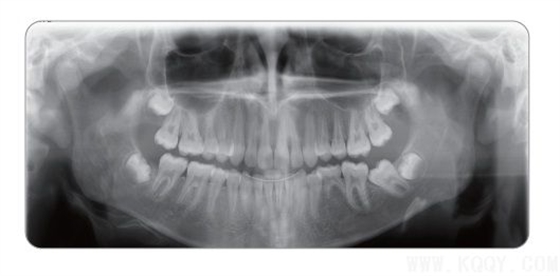

成人全景圖:顯示上下牙列、牙槽骨、神經管及TMU,圖像均勻,前牙區結構也可清晰顯示